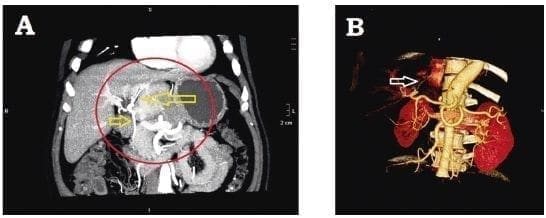

Habitualmente, la masa tumoral desplaza los órganos adyacentes (figura 2A) y comprime los vasos arteriales y venosos cercanos (figura 2B) 12,18,25. Ocasionalmente, puede presentarse compresión de la vía biliar 25. Mediante el uso de angiografía computadorizada y reconstrucción tridimensional, es posible observar que los vasos del tumor se originan de ramas de la arteria hepática (figura 3) 12,20.

Figura 2. A. Tumor fibroso solitario del hígado que desplaza la pared gástrica. B. Vasos sanguíneos desplazados y comprimidos por un tumor fibroso solitario hepático adyacente.

Figura 3. A. Irrigación arterial del tumor hepático, que se origina de la arteria hepática. B. Reconstrucción tridimensional que muestra los vasos que irrigan el tumor.